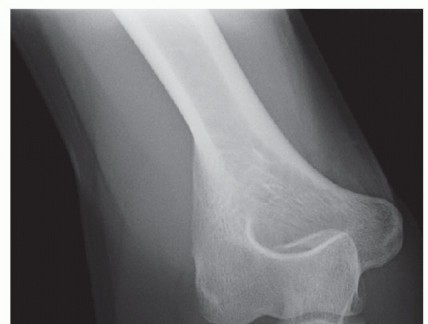

Anteroposterior (AP), lateral, and oblique views are the standard of care, but they may underestimate or overestimate joint impaction and degree of comminution.

A radiocapitellar view with forearm in neutral and at 45 degrees of flexion gives an improved view of the articular surfaces.

A sailboat sign can provide suspicion to an occult radial neck fracture.

If decision is made for operative treatment, we routinely obtain a computed tomography (CT) scan to better understand the fracture pattern for preoperative planning, so that operative time is efficient and to minimize intraoperative surprises. Three-dimensional reconstructions provide further information not always easily appreciated on routine CT scans.